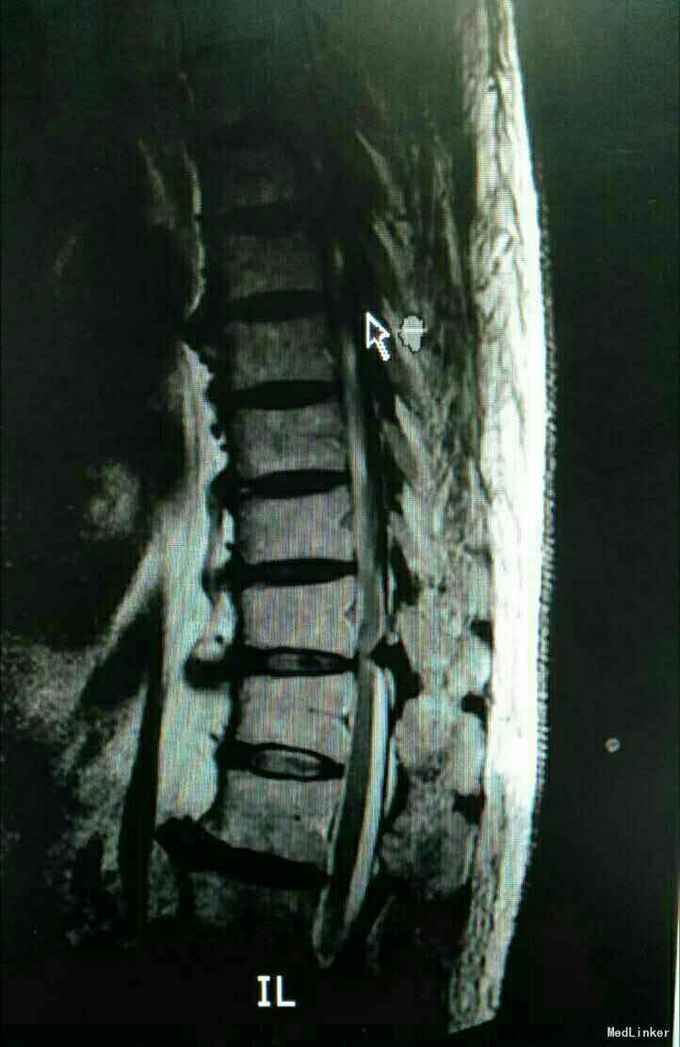

又是严重的胸椎黄韧带骨化,胸10-11、胸11-12。

渐进性双下肢感觉运动障碍10月,大小便障碍10天。